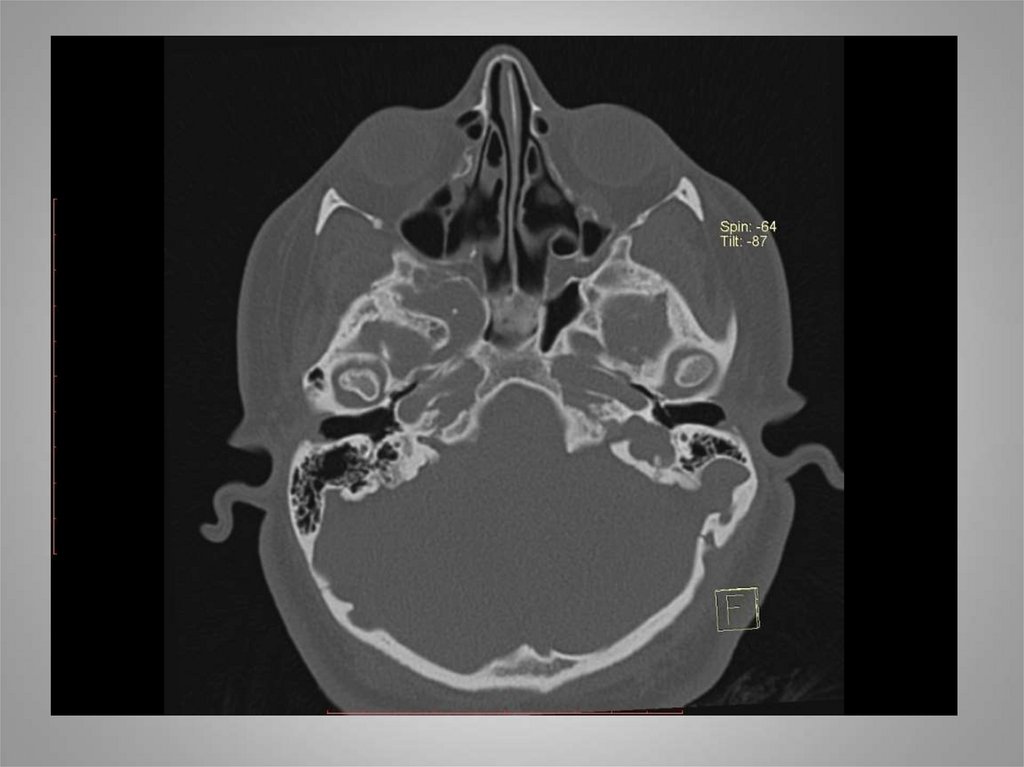

18. МСКТ

19.